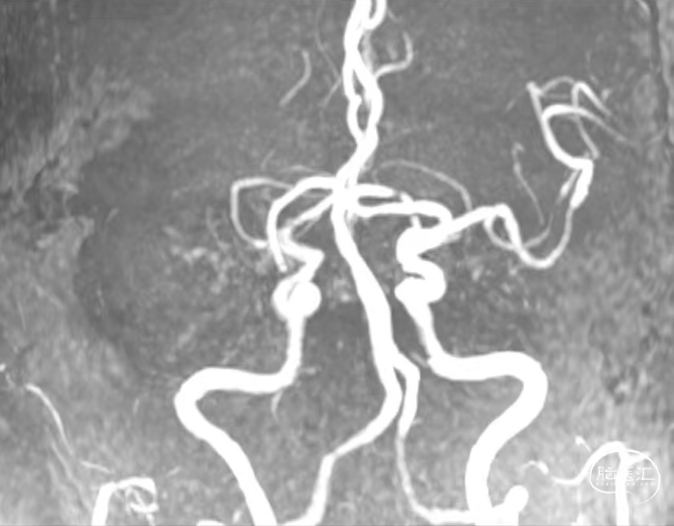

术前DSA造影

评估病变及代偿:Ⅰ型弓,右侧大脑中动脉闭塞,软脑膜动脉、大脑前动脉对其部分代偿,ASITN/SIR 2级。